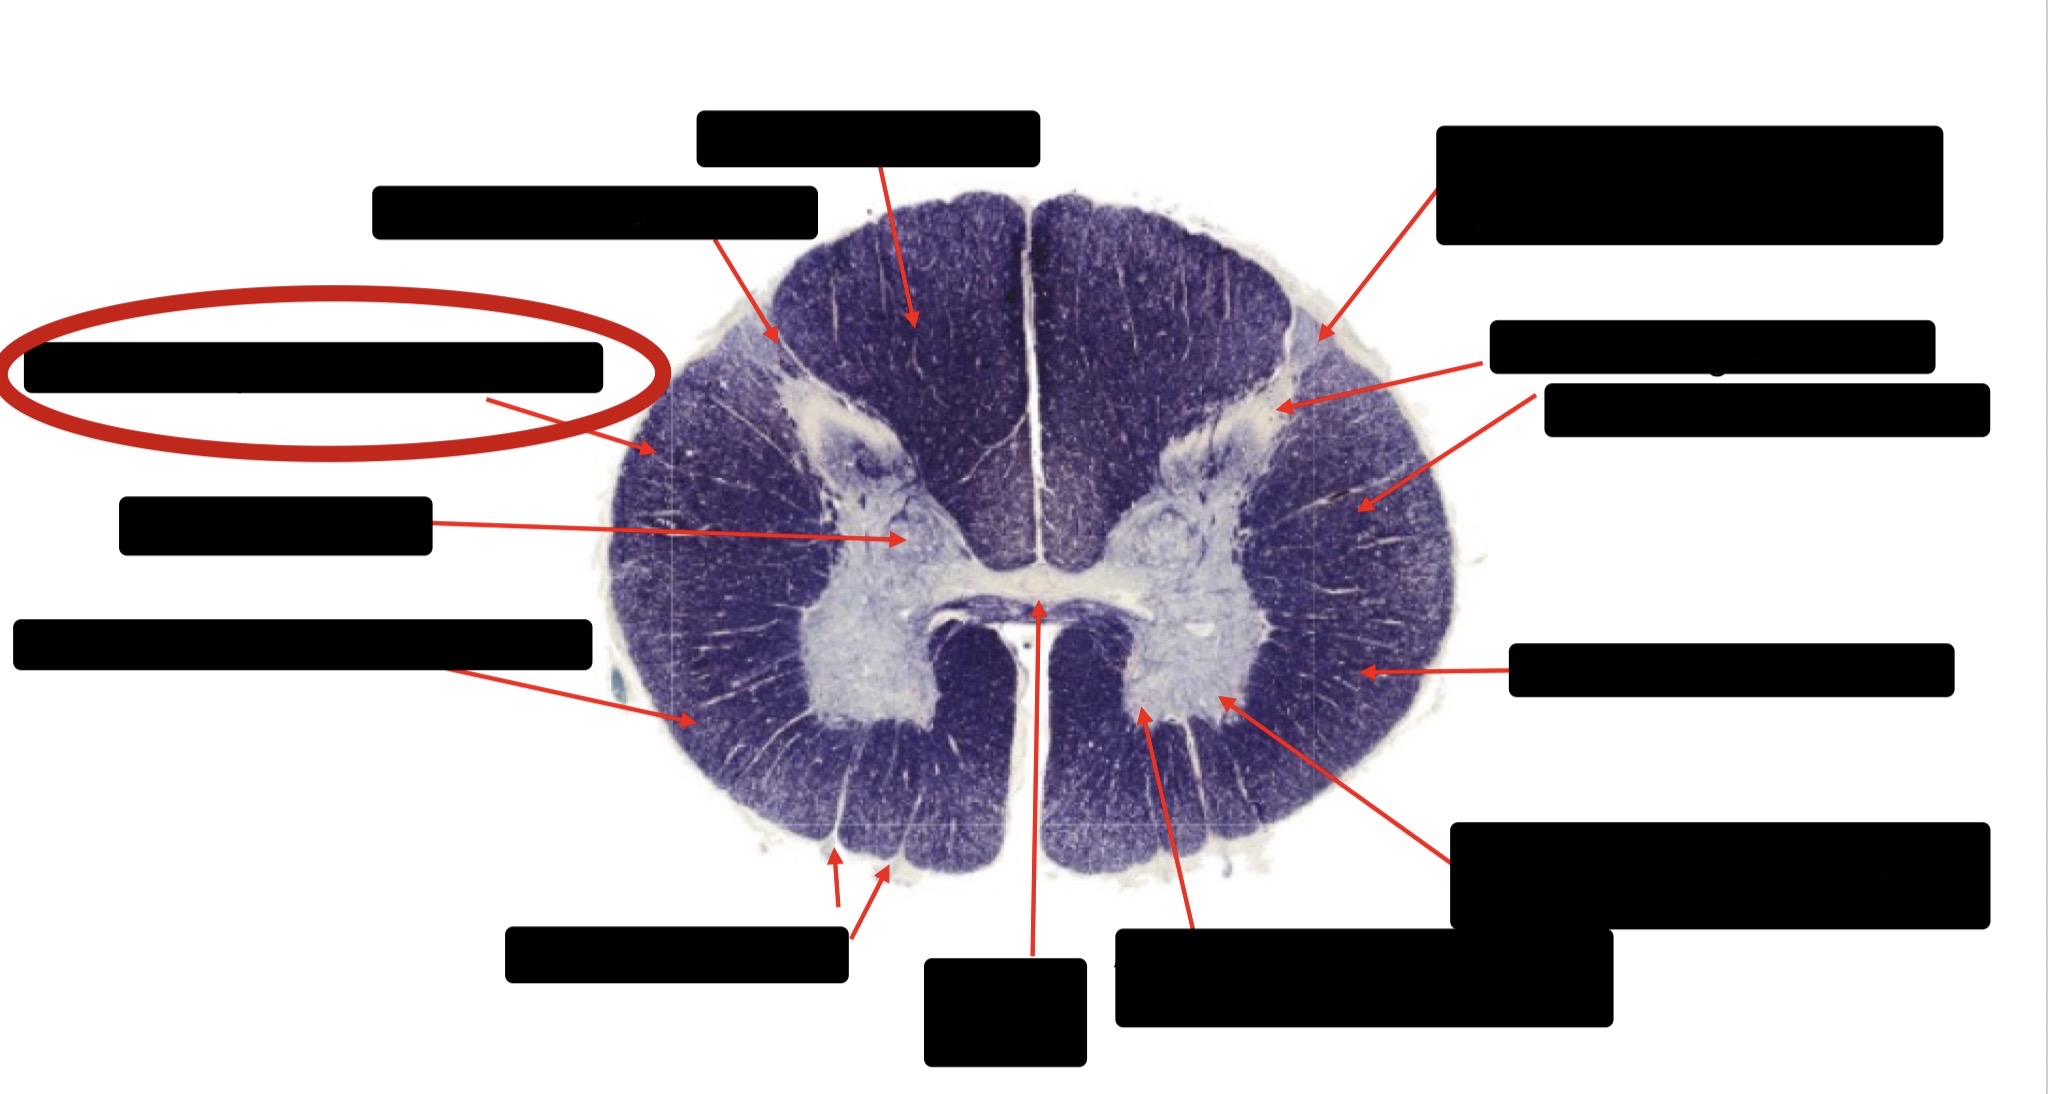

Posterior Column

Large Fiber Entry Zone

Posterior Spinocerebellar Tract

Clarke’s Nucleus

Anterior Spinocerebellar Tract

Ventral Root Fibers

Central Canal

Lissauer’s Tract & Small Fiber Entry Zone

Substantia Gelatinosa

Lateral Corticospinal Tract

Spinothalamic Tract

Anterior Horn Motor Neurons (Distal Muscles)

Anterior Horn Motor Neurons (Proximal Muscles)

Dorsal Rootlet

Lateral Horn

Spinothalmic Tract